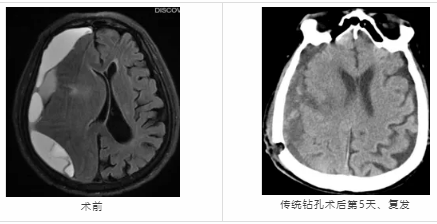

近日,隨州市中心醫(yī)院神經(jīng)外科成功為一名73歲慢性硬膜下血腫顱骨鉆孔引流術(shù)后復(fù)發(fā)患者實(shí)施神經(jīng)內(nèi)鏡下小骨窗慢性硬膜下血腫清除術(shù),患者術(shù)后恢復(fù)良好。 73歲的H大爺,十天前無(wú)明顯誘因開(kāi)始出現(xiàn)頭痛、頭昏,伴惡心, ...